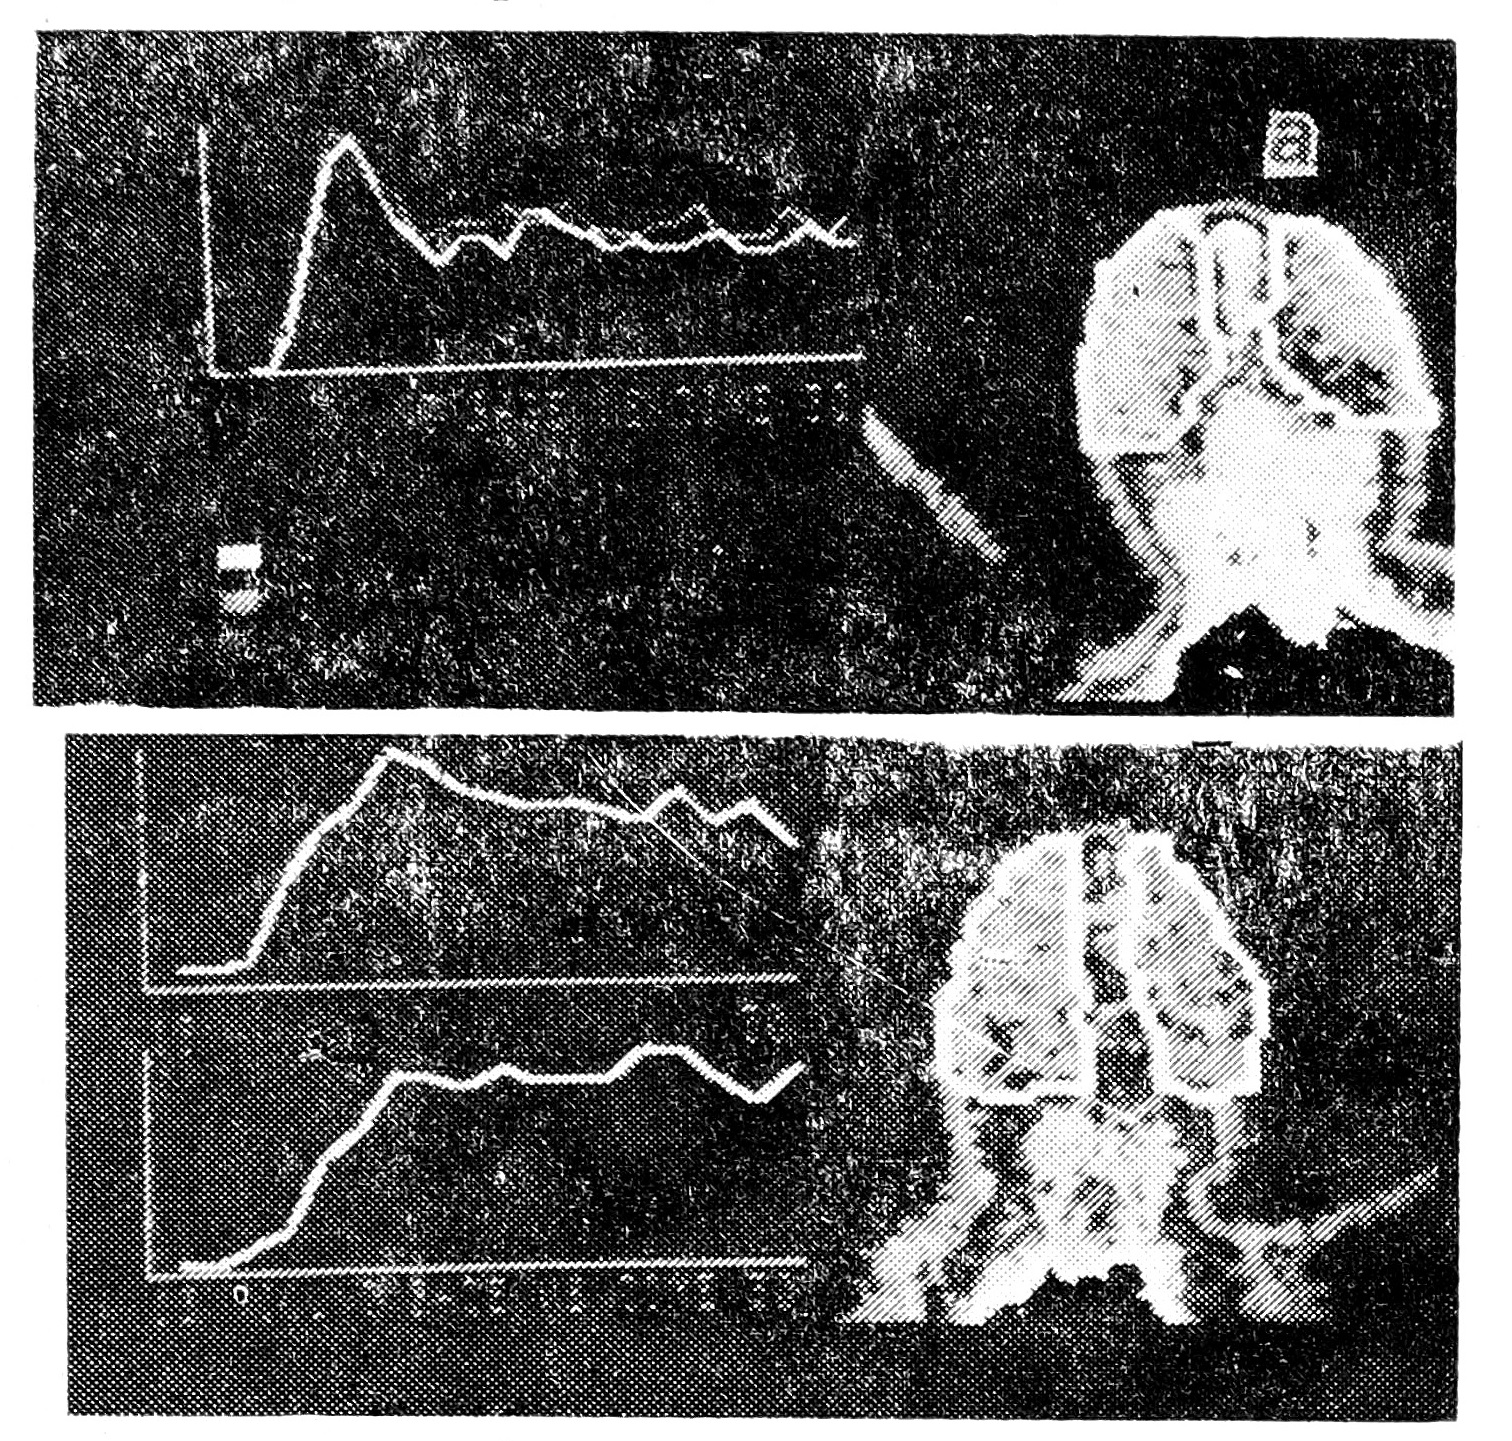

Динамическая энцефалосцинтиграфия была произведена 4 пациентам (третьему, четвертому, седьмому- и восьмому) на 8—13-е сутки жизни. У всех больных были выявлены диффузные изменения кровотока во всех исследуемых бассейнах артерий мозга, заключавшиеся в резком увеличении времени прохождения изотопа в артериально-паренхиматозной и венозной фазах, увеличении площади под кривой «активность—время» при нормальном значении ее максимальной амплитуды (рис. 2).

Рис. 2. Энцефалосцинтиграмма и кривые «активность — время» при герпетическом энцефалите: а — данные новорожденного ребенка без поражения головного мозга; б — увеличение времени артериальной и венозной фаз у новорожденного с герпетическим энцефалитом (2 недели жизни).